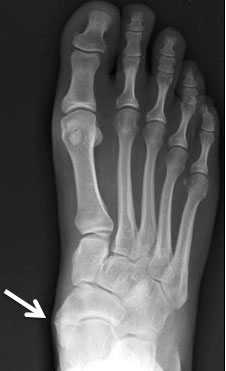

Рентгенограмма стопы при 1 типе добавочной ладьевидной кости

Рентгенограммы стоп: 3 тип добавочной ладьевидной кости